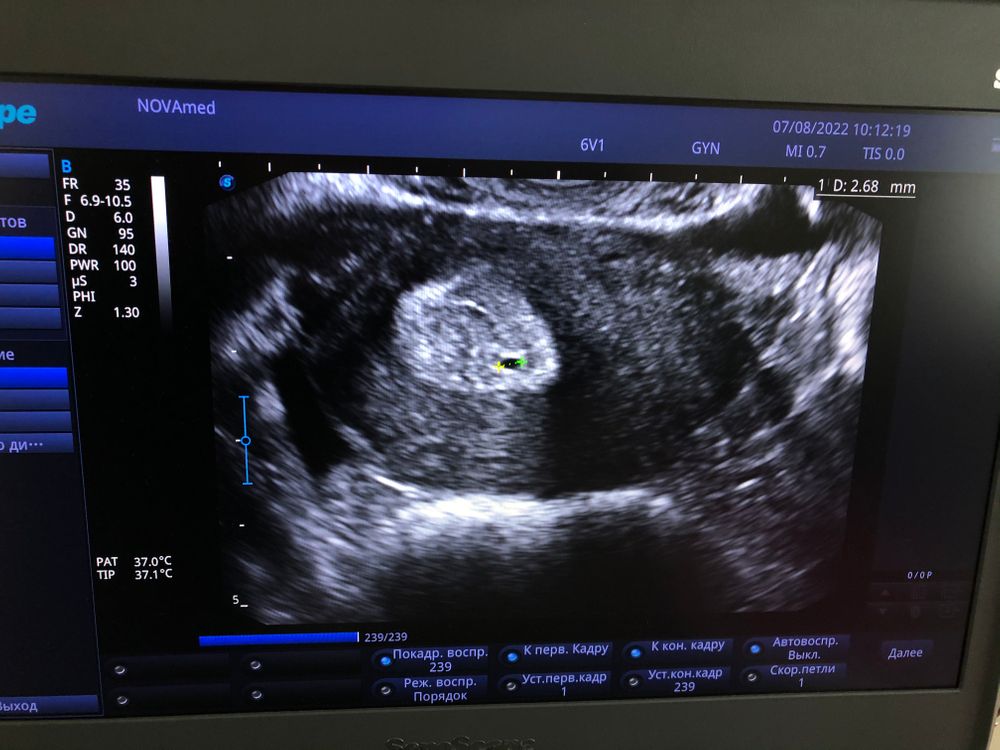

Kriss Miss, надеюсь😁 потому что я сходила сегодня на УЗИ и мне вообще странную картину выдали😁🤷🏼♀️🤦🏼♀️👇🏻 и надеюсь что образование в 12мм это и есть ДФ, поэтому предположительно дня через 2-3 должен совулировать! Но вот момент с плодным яйцом меня в ступор вводит🤯 может спутала с чем то! Потому что сегодня 19 дц, и М🩸 были как обычно! Правда задержка большая была!

Kriss Miss, вот такая картина. Она сказала сфотографируй и покажи гине

Это я так понимаю матка? Или яичник?🤣

Анастасия , матка , в матке точка ) по этому она и написала Б) скорее тестик , мне потом скиньте ❤️